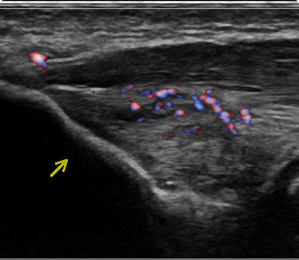

Orthopedische echografie, een blessure nader bekeken .........